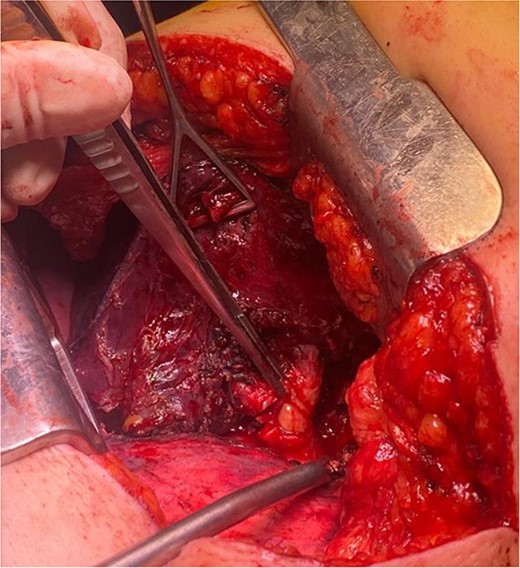

Bronchoscopy report confirming a mass completely occluding the left upper lobe and lingula (Fig. 3). Endobronchial lipoma along the left main bronchus (white arrowhead).

The patient underwent left-sided thoracotomy and upper lobectomy due to severe parenchymal inflammation and necrosis of the left upper lobe, with histopathology confirming a well-circumscribed adipocytic lesion consistent with lipoma measuring ~9.1 × 6.9 × 9.3 mm in the bronchus (Figs 3 and 4). Adjacent lung tissue exhibited organizing pneumonia and bronchiectasis. Post-operatively, she recovered well and was discharged home in stable condition on the fourth day.

In our presented case, surgical resection in the form of left upper lobectomy was ultimately required due to severe parenchymal inflammation and necrosis. This decision highlights the critical role of surgical intervention in cases where endobronchial lipomas cause significant structural lung damage or fail to respond adequately to bronchoscopic management.